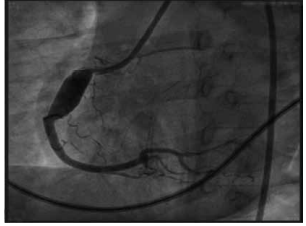

Essa é uma angiocoronariografia realizada por um paciente. Assinale a alternativa que indica, corretamente, qual é o diagnóstico etiológico e qual é o tratamento que deveria ser instituído na suspeita diagnóstica.